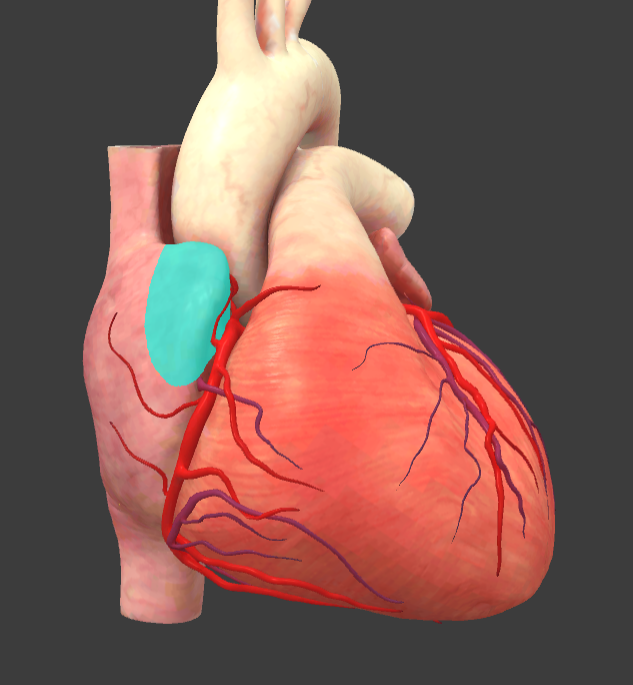

Left auricle

Right auricle

Left auricle

Right auricle